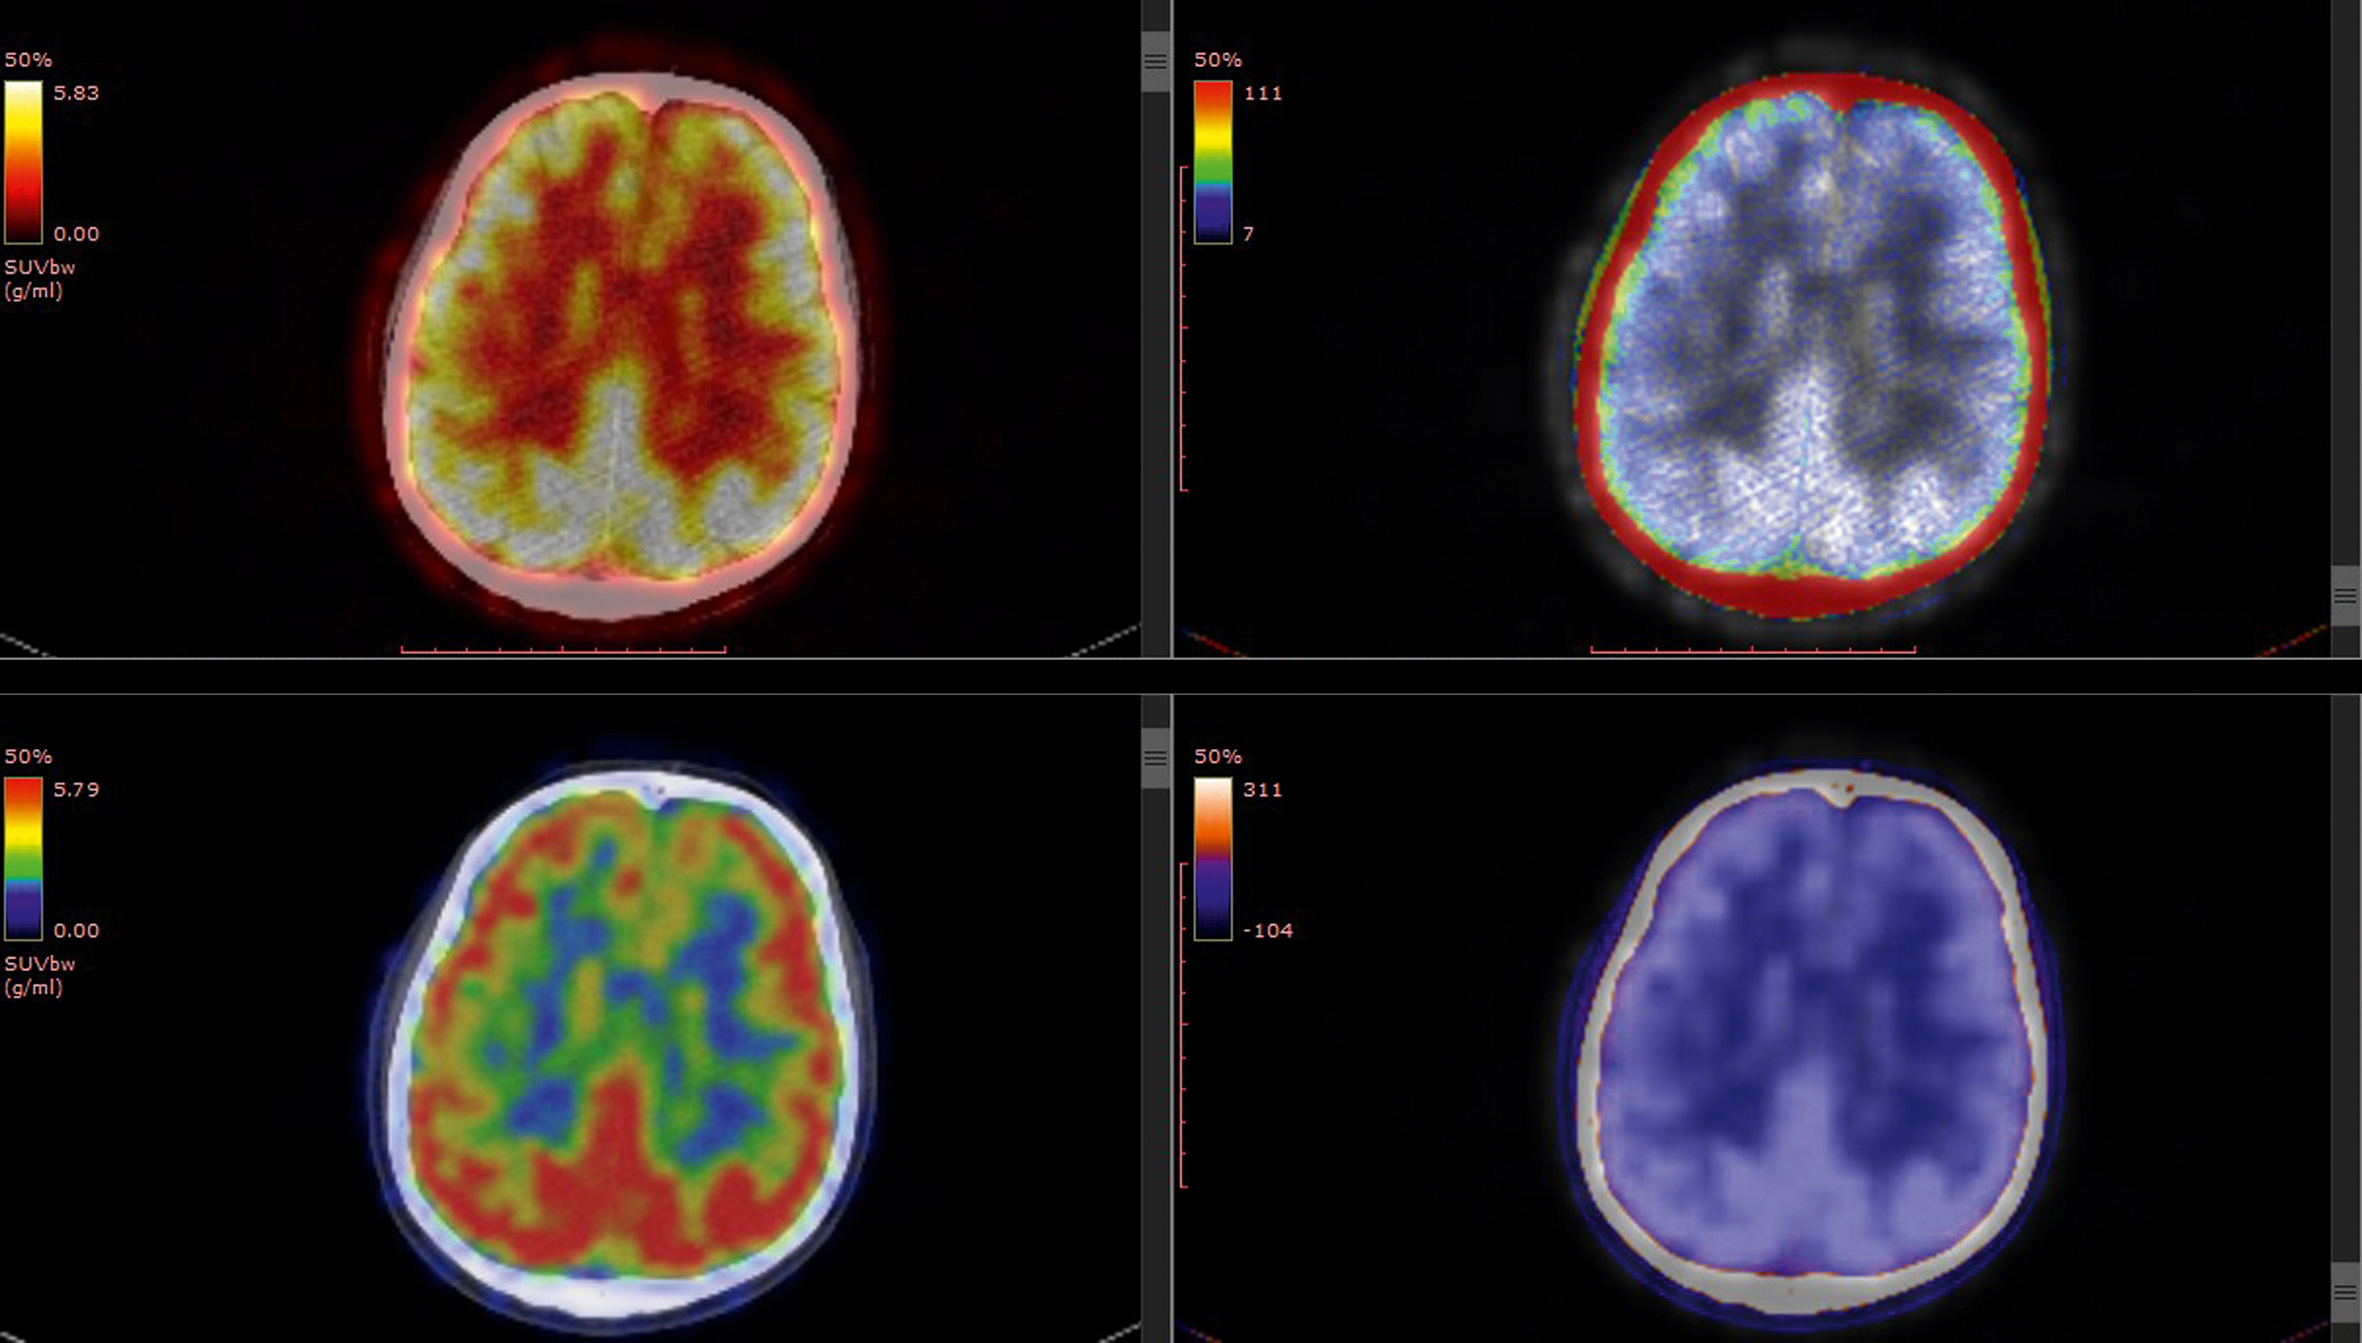

Previously... au Centre de la mémoire

L’Assemblée générale AMYPAD (The Amyloid imaging to prevent Alzheimer’s disease) s’est tenue les 10 et 11 octobre dernier. Cette rencontre, qui a réuni plus de 80 participants à Barcelone, a permis de discuter de l’avancé des études cliniques intégrées dans ce projet. Genève fait partie des 8 sites européens qui ont reçu l’approbation pour l’étude diagnostique et des 9 sites européens qui ont reçu l’approbation pour l’étude pronostique. Le deuxième jour a été consacré à la présentation des travaux scientifiques liés à ces études. Neuf chercheurs ont ainsi pu exposer leurs travaux, dont deux du Centre de la mémoire, notamment ceux sur le PET-amyloïde réalisé de façon précoce pour améliorer la confiance diagnostique des médecins.

Les conclusions principales ont montré que les biomarqueurs tau ont un niveau de maturité variable : les marqueurs dosés dans le liquide céphalorachidien ont atteint le niveau plus élevé d’évidence, ainsi qu’un des traceurs d’imagerie PET de première génération. Les biomarqueurs plasmatiques ont montré des résultats prometteurs en termes de validité analytique pour les protéines tau et amyloïde et ouvrent des nouvelles perspectives pour une utilisation à large échelle. La définition de biomarqueurs fiables pour le diagnostic précoce de la maladie d’Alzheimer est une priorité cruciale partagée par la communauté mondiale de la recherche et des cliniciens.